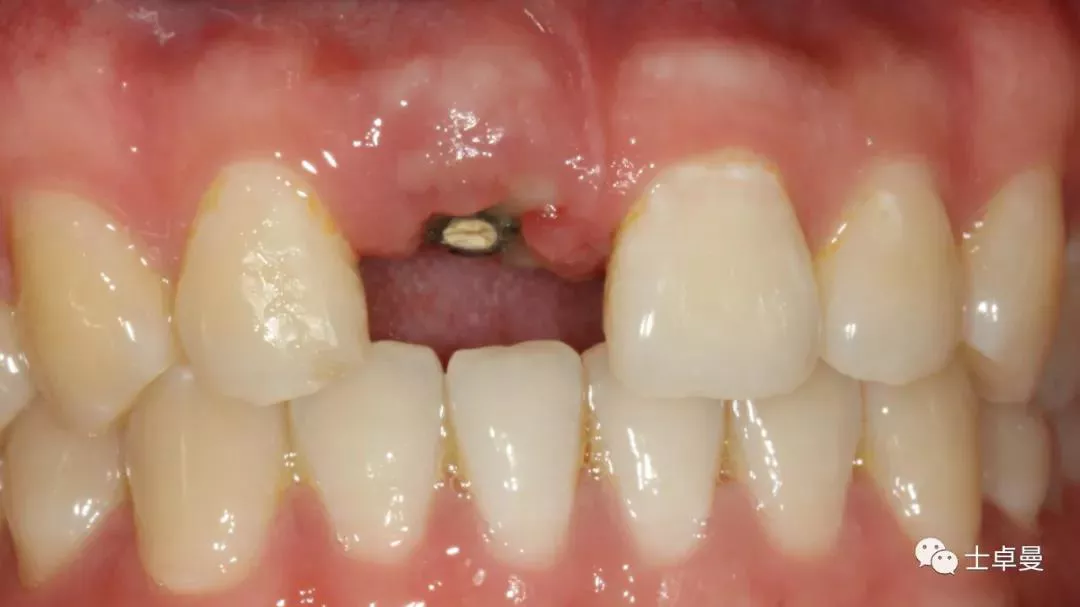

口内检查

· 11牙冠折断,余留残根;

· 唇侧位于龈上2mm,腭侧达骨下1mm,根管内封药存;

· 探(-),冷 (无反应),叩 (-),松 (-),牙龈可;

· 中位笑线,牙龈生物型为中弧形、中厚龈生物型;

分根

拔出腭侧牙根

保留唇侧牙片

牙周探针探查牙片位置及松动度